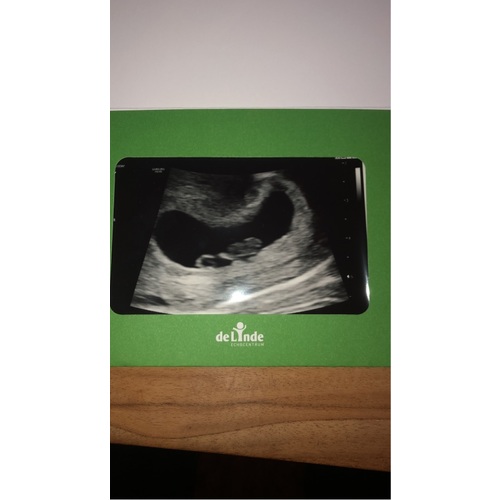

Pff dat is heel naar om mee te maken! Ik snap dat je het nu extra spannend vindt. Dit was onze echo met 7 weken. Links de dooierzak en rechts de baby.